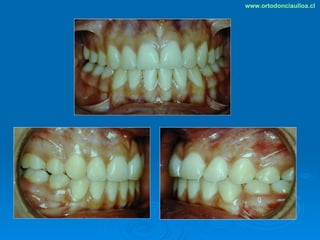

Este documento presenta dos casos clínicos de pacientes que recibieron tratamiento de ortodoncia. El primer caso fue de una paciente femenina de 14 años con apiñamiento dental y mordida cruzada que fue tratada mediante extracción de premolares y alineamiento dental. El segundo caso fue de un paciente masculino de 14 años con clase II esqueletal y desarmonía dentomaxilar que fue tratado con extracción de premolares y corrección de mordida. Ambos casos mostraron mejoría después de 3 años de tratamiento.